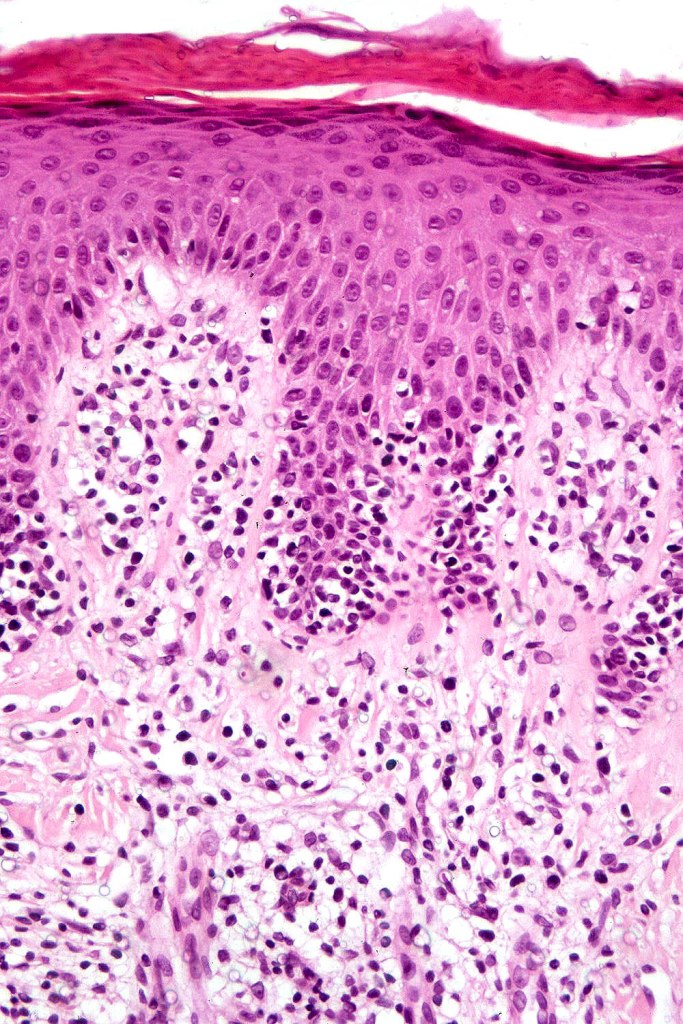

Histological features

The histological hallmark of mycosis fungoides is the presence of large atypical lymphocytes with a convoluted/cerebriform nuclear border (Sézary cells). These may be found at the epidermal-dermal jnuction and as collections within the epidermis (Pautrier microabscess). These are most easily found in plaque stage disease. The epidermal component can be subtle in patch stage disease and is often lost in tumor stage dsease. The classification into patch, plaque & tumor stage disease is less helpful histologically as the features merge from one to the other. It is all a matter of degree.

Plaque Stage Disease

•Compact hyperkeratosis & patchy parakeratosis

•Acanthosis

•Psoriasiform hyperplasia common

•Epidermotropism is often marked with conspicuous Pautrier microabscesses

•Lichenoid variant & poikiloderma atrophicans vasculare

•Variable folliculotropism (+/- mucinosis) & syringotropism

•Coarse collagen bundles in papillary dermis

•Superficial band-like dermal infiltrate of atypical lymphocytes, eosinophils, plasma cells & histiocytes